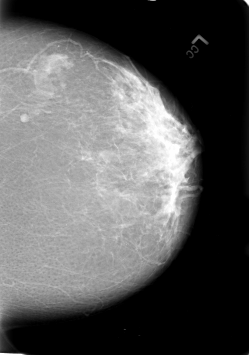

B_3020_1.LEFT_MLO

LEFT_MLO LINES 5672 PIXELS_PER_LINE 4160 BITS_PER_PIXEL 12 RESOLUTION 50 NON_OVERLAY